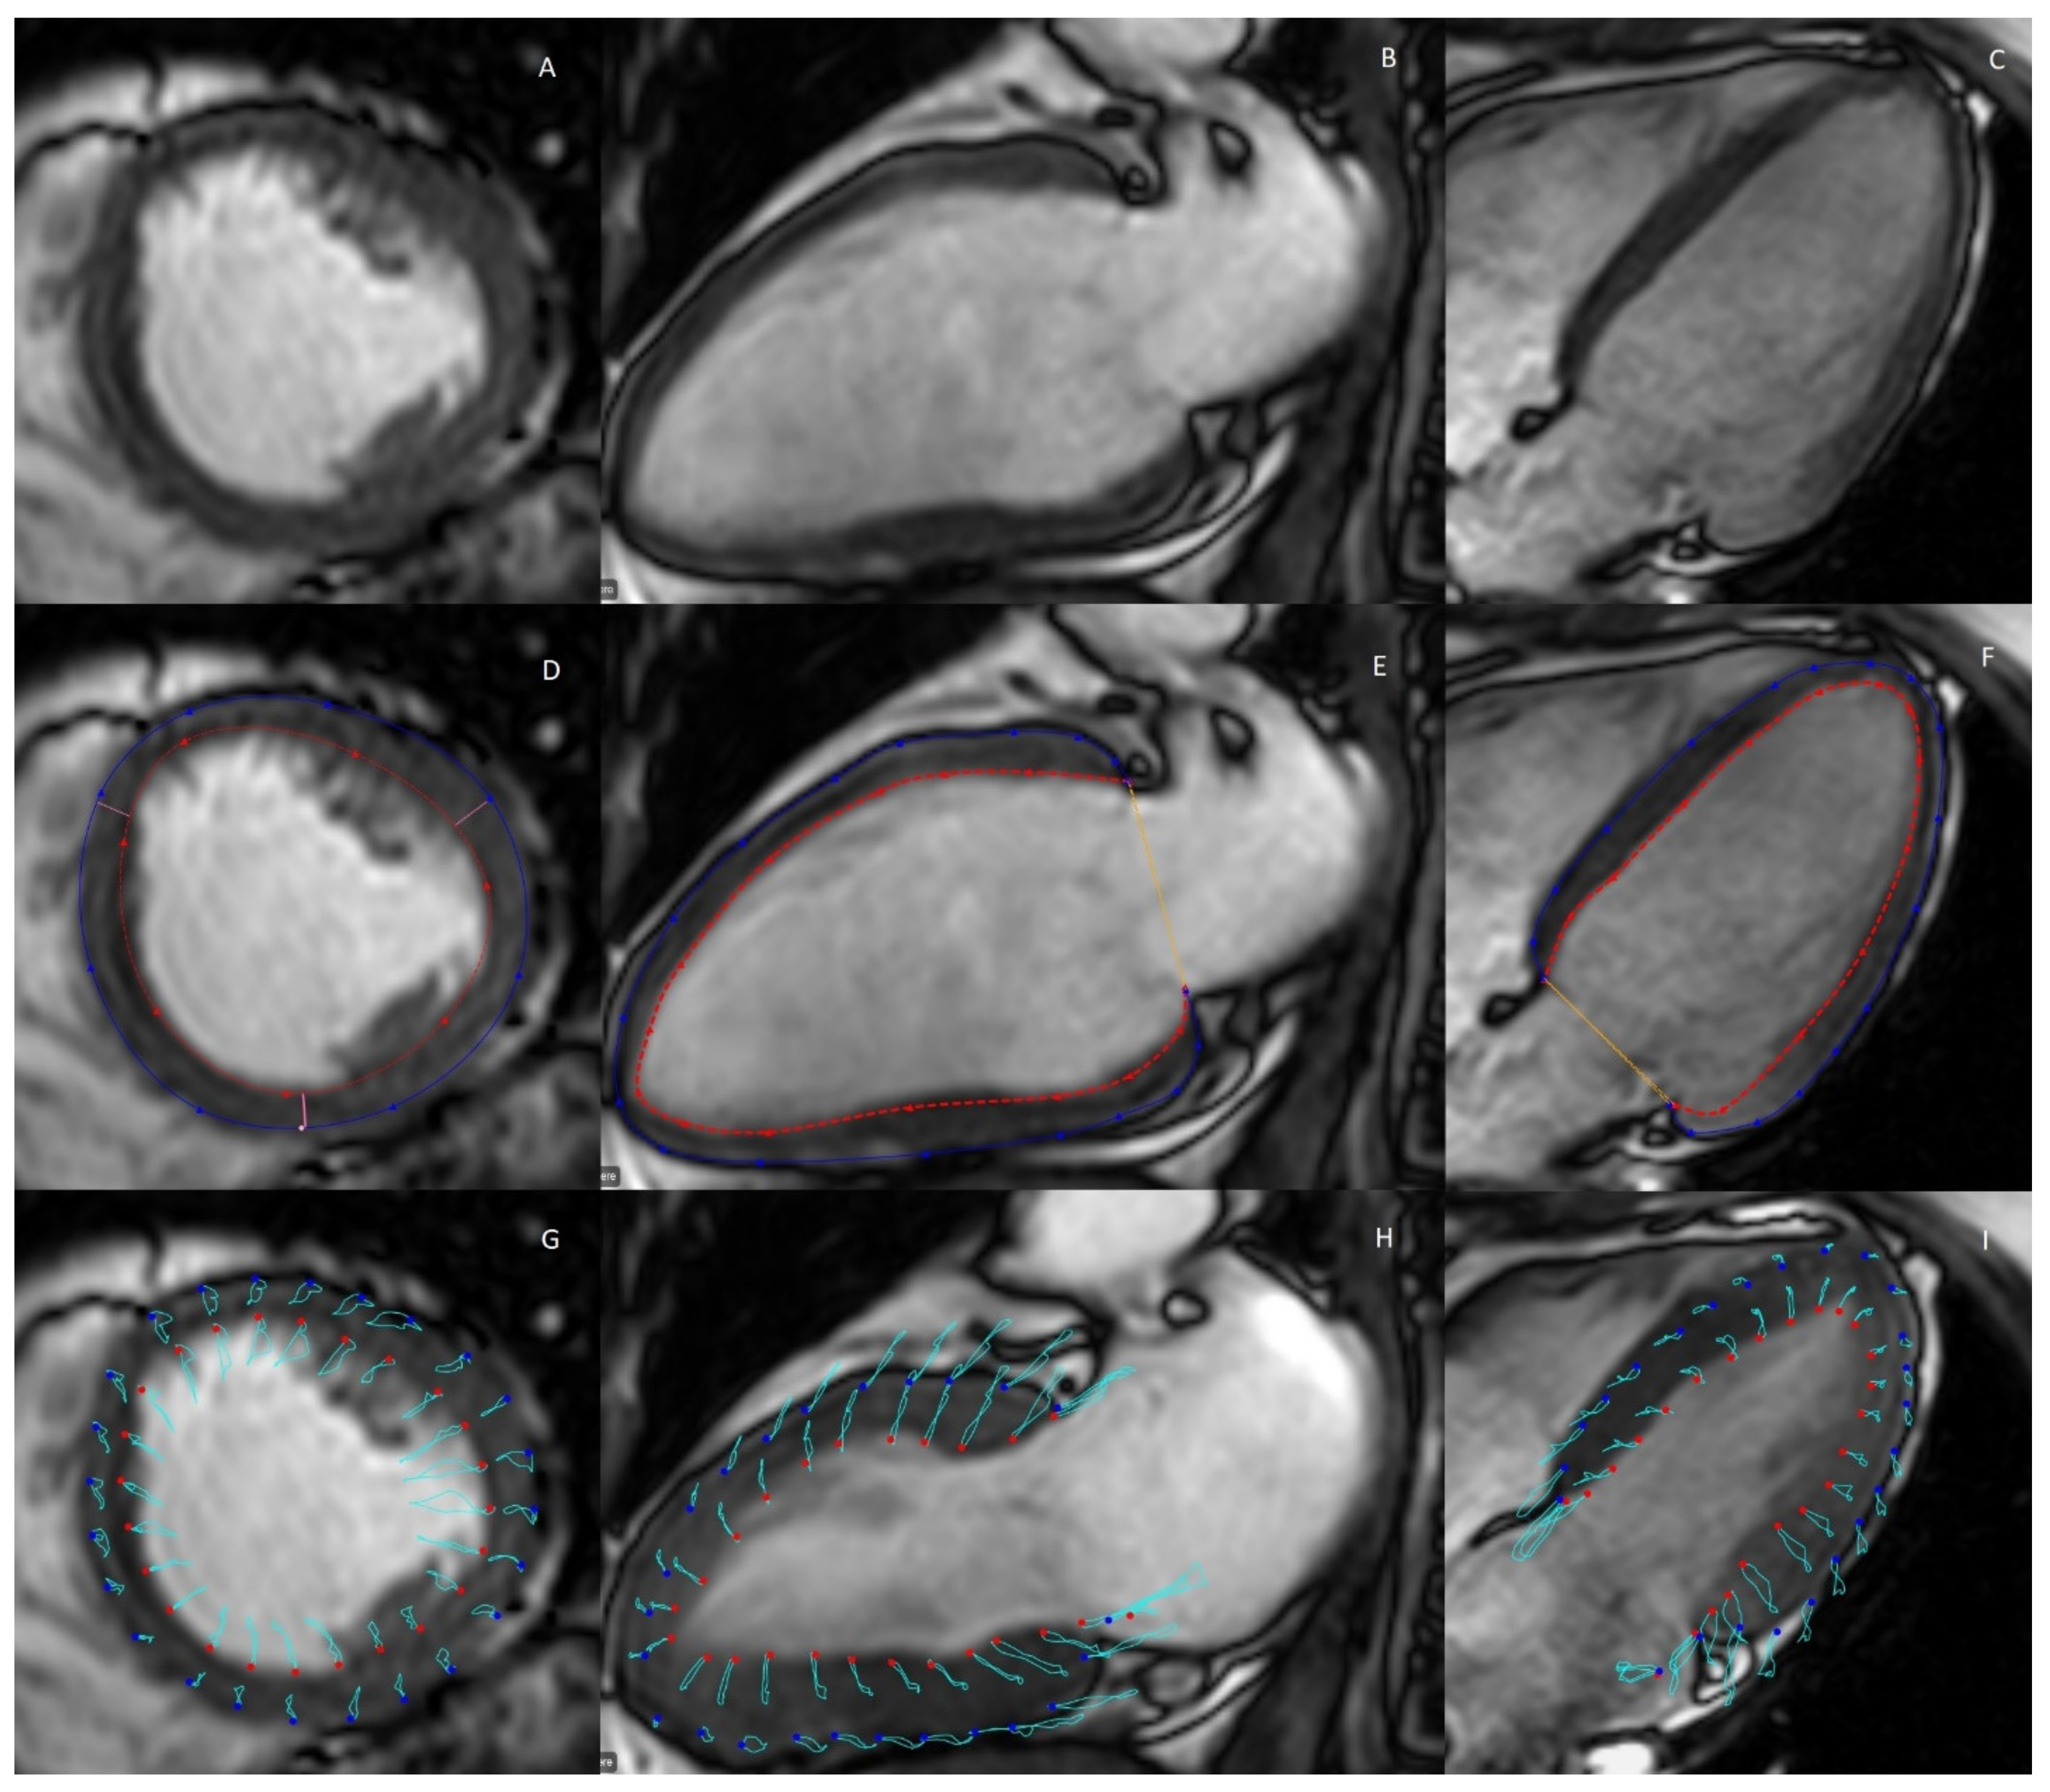

2.3. Myocardial Strain